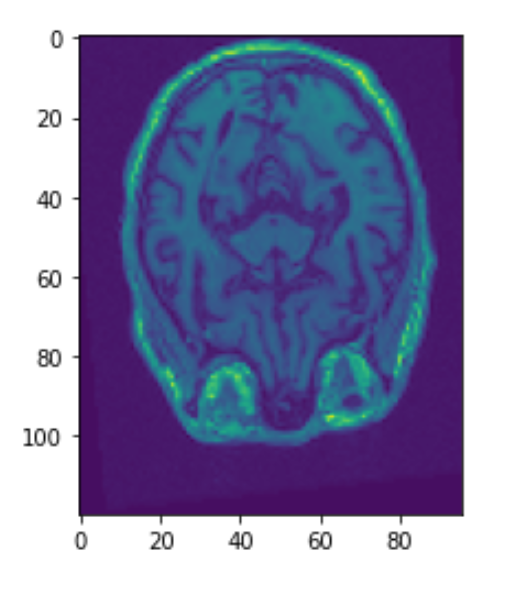

Before any analysis can be done with MRI scans, image registration must be done. Patients can be in many positions when they get their scans. The heads may be slightly tilted or rotated. Image registration normalizes the dataset so that the skulls are somewhat aligned. Below we can see the third image aligned using SimpleElastix. The 2nd image was rotated and moved slightly. The first and third image should line up well.